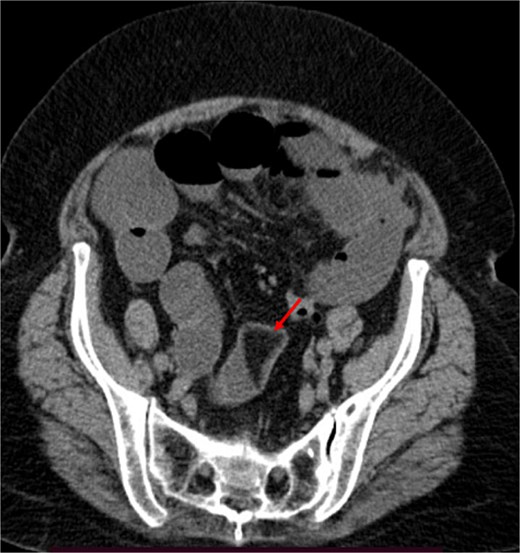

A contrast-enhanced CT of the abdomen was performed and revealed an intraluminal mass in the pylorus causing gastric dilatation (Fig. 1) and another intraluminal mass in the terminal ileum causing small bowel dilatation (Fig. 2). A nasogastric tube was inserted, and the patient was taken for exploratory laparotomy. There were significant gastric and small bowel dilatations; a gastrostomy and enterostomy were performed, and two foreign bodies were extracted (Fig. 3). The incision sites were then repaired.

Two foreign bodies were extracted from the stomach and small bowel.